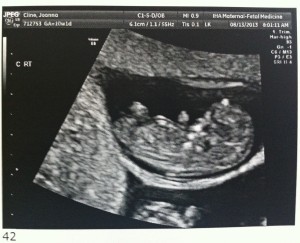

Hello! Today was the all important 12 week ultrasound and everything was great! The fetuses are all measuring about 2.5 inches and their hearts are beating strong. They also like to wiggle around a lot which created some challenges for the very patient ultrasound tech. (With three fetuses to measure, it took about 90 minutes.)